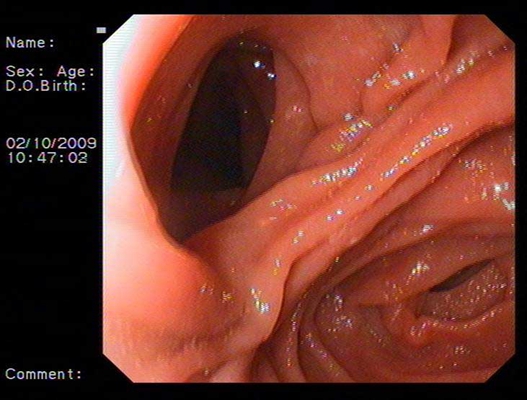

食道炎圖片